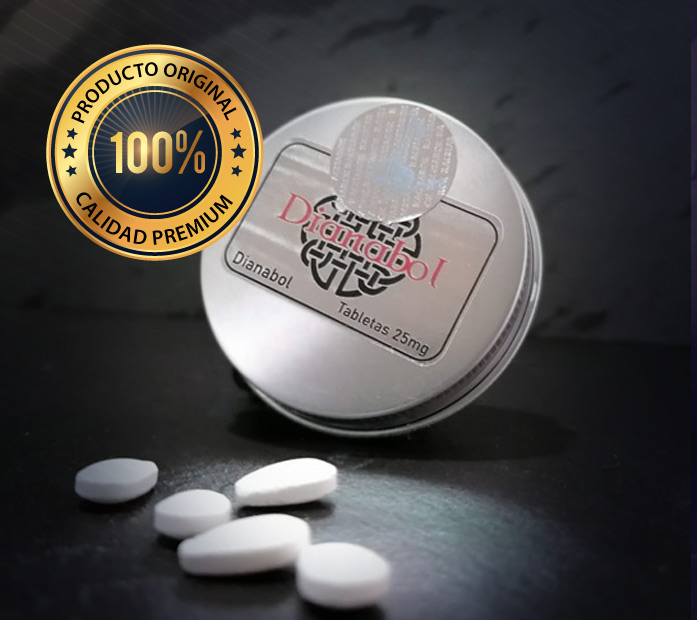

Mantenemos altos estándares de calidad a la hora de fabricar nuestros potenciadores anabólicos-androgénicos. En RAGNAROK LAB® promovemos el deporte, la competitividad, la fuerza y la perfección corporal. Lideramos la industria de los fármacos deportivos con fórmulas reales. Ya sean orales o viales, notarás la diferencia en cualquier ciclo de corte, definición, ganancia o post.

Contamos con la distribución oficial de las marcas más reconocidas en México y a nivel mundial, nuestros precios son los más bajos del mercado, nosotros somos distribuidores directos de los laboratorios y no tenemos intermediarios. Enviamos a todo México por paquetería y es gratis al ordenar más de 3 productos, los cuales se envian al siguiente día de haber ralizado su pedido.

RAGNAROK LAB® ofrece la mayor variedad de productos nutricionales de la más alta calidad.